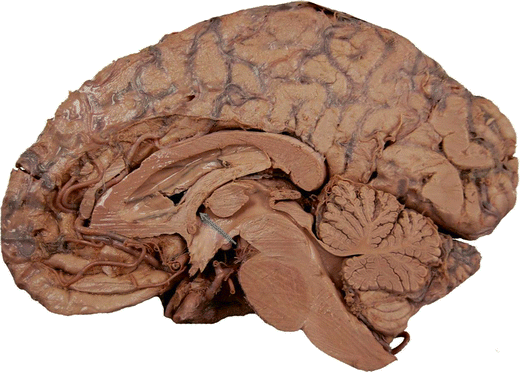

Midsagittal section of a cadaveric brain illustrating the right foramen of Monro (arrow)